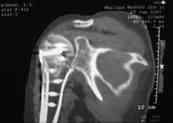

Диагноз: неправильно сросшийся в условиях накостного остеосинтеза оскольчатый перелом головки левой плечевой кости (11-С3.2), асептический некроз головки плечевой кости, смешанная артро-миогенная контрактура левого плечевого сустава; демиелинизирующая нейропатия левого локтевого нерва.

Анализ ситуации позволяет считать, что основными причинами контрактуры являются неправильная репозиция фрагментов головки (разворот кверху и кзади), асептический некроз головки плечевой кости (отчетливое склерозирование на СТ).

2. Сохранение металлоконструкции с удалением выступающих за пределы головки винтов, релиз сустава, заполнение дефекта (b5_ct.jpg) на стыке метафиза и головки аутотрансплантатом для устранения «триггера», ранняя реабилитация.